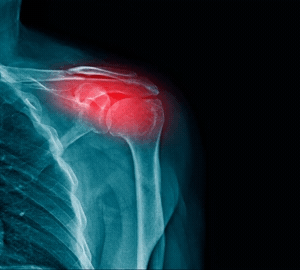

Swelling: Inflammation and swelling around the affected joints.

Causes of Joint Pain in Upper Extremities

Symptoms of Joint Pain in Upper Extremities